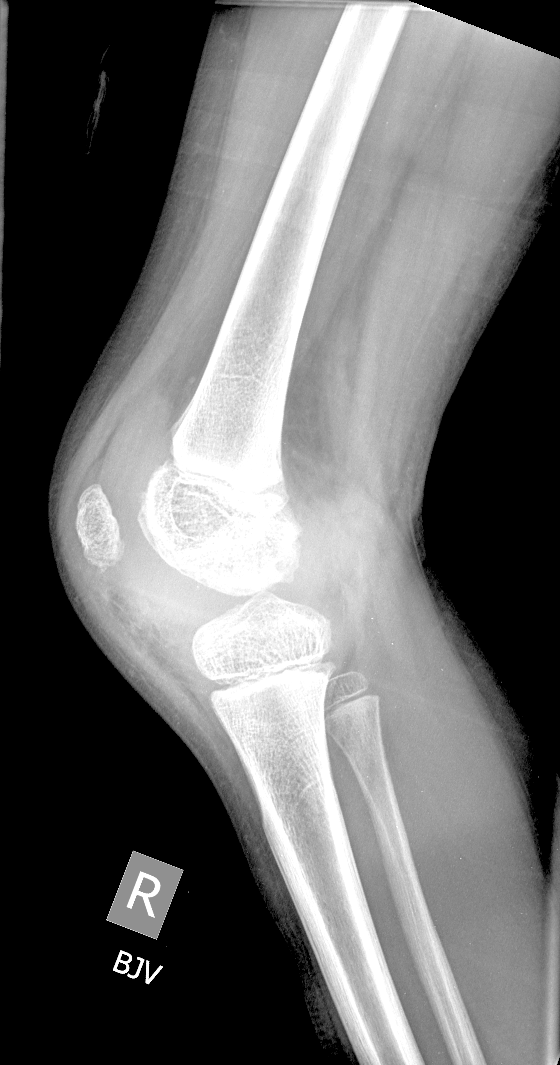

Info Images Findings Impression Reco/Acuity Case Images View Images / Launch Visage Case Notes History 2-month-old presents with decreased right arm movement, increased fussiness, and increased sleepiness for 2 days. Suspected non-accidental trauma. Exam Skeletal survey Prior Study none Dicom View Reference Material

Section 1 Submit Findings CB1550 Findings Skeletal Survey - Technique Check Skull AP/Lat Yes No Cervical and Thoracolumbar spine Yes No Chest X-Ray Yes No Ribs – Left/Right Oblique Yes No Abdominal X-Ray Yes No Pelvis with both hips Yes No Bilateral Humerus, Forearm, Hand Yes No Bilateral Femur, Tibia/fibula, feet Yes No Any additional lateral views of the extremities Yes No The exam is over or under penetrated. Yes No The exam may or may not be limited by overlying structures or soft tissues, body habitus, patient positioning, support devices, or motion. Yes No The area of concern is indicated by the patient, technologist, or care provider. Yes No The area of concern is included on the exam. Yes No Soft Tissues There is soft tissue swelling, indistinctness of fat/muscle planes, gas, or laceration in the area of clinical concern. Yes No There is an effusion, fat pad displacement, or fat fluid level. Yes No There is a radiodense or lucent foreign body. Yes No There are other densities, calcifications, post-surgical changes, or support devices in the soft tissues. Yes No Any support lines/tubes. Yes No Bone There is a break or interruption of the continuity of the cortical or cancellous bone. Yes No There is overriding of the trabeculae with apparent sclerosis. Yes No There is displacement of a fracture fragment. Yes No There is bowing of the bone in addition to the fracture at the apex of the bowed bone concerning for the greenstick. Yes No There is a spiral fracture of the leg concerning for toddler’s fracture. Yes No There is abnormal angulation or bulging of the cortical surface relative to the normal cortex which could be from a buckle or torus fracture. Yes No There is a displaced fragment which may be from avulsion by a tendon, ligament, or joint capsule or from a comminuted or other fracture. Yes No The stress trabeculae or other trabeculae of the cancellous bone are interrupted or otherwise abnormal. Yes No There is subperiosteal or endosteal reaction which could indicate a healing or subacute fracture or other abnormality. Yes No There is hard/soft callus formation. Yes No There is remodeling of the bone. Yes No There is a corner fracture or metaphyseal lesion that could be from nonaccidental trauma. Yes No There are multiple fractures of different ages. Yes No There are vertebral body/spinous process fractures. Yes No There are rib fractures. Location - posterior or lateral. Yes No There is scapular/sternal fracture. Yes No There are fractures of the digits. Yes No There are wormian bones. Yes No There are intrasutural bones. Yes No There is metaphyseal abnormality (lucencies, increased density, erosion) which may be from something other than injury such as stress, metabolic disease (e.g. rickets with loss or distortion of the zone of the provisional calcification), neoplasm (e.g. leukemia), heavy metals, inflammation, or infection. Yes No There are metaphyseal spurs. Yes No There are bony deformities involving multiple bones. Yes No The bones are gracile. Yes No There are non-healing fractures. Yes No There is/are focal or multifocal lytic/lucent, blastic/sclerotic or mixed density lesion(s) or other abnormality. Yes No Overall bone density is increased or decreased with or without thinning or thickening of the cortical or cancellous bone. Yes No Growth plates, ossification centers, apophyses The growth plate(s) is/are abnormal. Yes No There is widening of the physis from a fracture with or without displacement of the epiphysis (Salter-Harris I). Yes No There is a fracture through the physis which then extends into the metaphysis with or without angulation or displacement (S-H II). Yes No There is a fracture through the physis which then extends into the epiphysis and is intra-articular, with or without angulation or displacement (S-H III). Yes No There is a fracture through the metaphysis, physis, and epiphysis which extends into the joint space with or without angulation or displacement (S-H IV). Yes No There is narrowing of the physis from a compression fracture (S-H V). Yes No The apophysis, epicondyle, secondary ossification center, or accessory ossicle is displaced or otherwise abnormal. Yes No The ossification centers are underdeveloped. Yes No Joints and alignment There is an effusion, fat pad displacement, or fat fluid level. Yes No The epiphysis or subchondral bone is fractured, interrupted, flattened, compressed, impacted, displaced, or otherwise abnormal. Yes No There is an intra-articular loose body or chondrocalcinosis. Yes No The joint is widened, narrowed, dislocated, malaligned, or incongruent. Yes No There is pseudoarthrosis. Yes No Other findings There are developmental changes or other anatomic variants or other existing conditions that may or may not be contributing to symptoms which can or should be further evaluated non-emergently or are otherwise incidental. Yes No The remainder of the exam is abnormal for age. Yes No The lungs show focal airspace opacity. Yes No There is pneumothorax. Yes No There is organomegaly. Yes No There is intra-abdominal calcification. Yes No There is displacement of the bowel loops. Yes No There is free intraperitoneal air. Yes No The bowel loops are dilated/obstructed. Yes No There is paraspinal soft tissue abnormality. Yes No